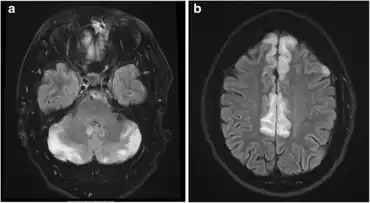

Diagnostic methods for hypertensive encephalopathy include physical examination, blood pressure measurement, blood sampling, ECG, EEG, chest X-ray, urinalysis, arterial blood gas analysis, and imaging of the head (CAT scan and/or MRI). Since decreasing the blood pressure is essential, anti-hypertensive medication is administered without awaiting the results of the laboratory tests. Electroencephalographic examination detects the absence of alpha waves, signifying impaired consciousness. In people with visual disturbances, slow waves are detected in the occipital areas.